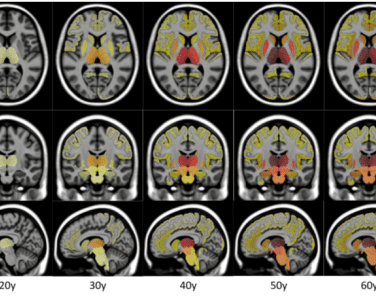

Une IA décèle les premiers signes de la sclérose en plaques. Ces recherches ont pour but de mieux comprendre comment la maladie évolue, mais également de diagnostiquer le patient avant l’apparition des premiers symptômes. Comment ? En développant des méthodes statistiques et de l’IA afin de construire des modèles d’évolution des structures cérébrales.